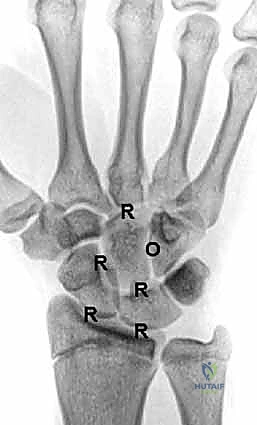

لفهم سبب تعقيد التهاب الرسغ وضرورة عملية التثبيت، يجب أن نلقي نظرة عميقة على التشريح المذهل لهذا المفصل. الرسغ ليس مفصلاً واحداً، بل هو مجموعة من المفاصل المتداخلة:

- عظم الكعبرة (Radius): العظم الرئيسي في الساعد الذي يحمل معظم وزن اليد.

- عظم الزند (Ulna): العظم الأصغر في الساعد، ويساهم في دوران المعصم.

- الصف الداني من عظام الرسغ (Proximal Row): يتكون من العظم الزورقي (Scaphoid)، الهلالي (Lunate)، والمثلثي (Triquetrum). هذا الصف هو الذي يتمفصل مباشرة مع عظم الكعبرة.

- الصف القاصي من عظام الرسغ (Distal Row): يتكون من العظم المربعي (Trapezium)، شبه المنحرف (Trapezoid)، ذو الرأس (Capitate)، والكلابي (Hamate). هذا الصف يتمفصل مع عظام المشط في اليد.

يُغطى كل سطح من هذه العظام بـ غضروف زجاجي (Hyaline Cartilage) أملس يسمح بانزلاق العظام فوق بعضها البعض دون احتكاك. عندما يُدمر هذا الغضروف (بسبب العمر، المرض، أو الإصابة)، تصبح الأسطح العظمية خشنة، وتنمو نتوءات عظمية (Osteophytes)، وتتمزق الأربطة، مما يؤدي إلى انهيار هيكلية الرسغ بالكامل.